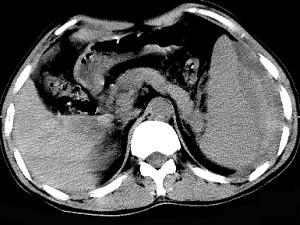

男、52岁1小时前车祸,伤及左季肋区,CT扫描如图,最可能的诊断是 ( )A、脾脓肿B、脾淋巴瘤C、脾破裂D、脾血管瘤E、脾梗死

问题 男、52岁1小时前车祸,伤及左季肋区,CT扫描如图,最可能的诊断是 ( )

选项 A、脾脓肿 B、脾淋巴瘤 C、脾破裂 D、脾血管瘤 E、脾梗死

答案 C